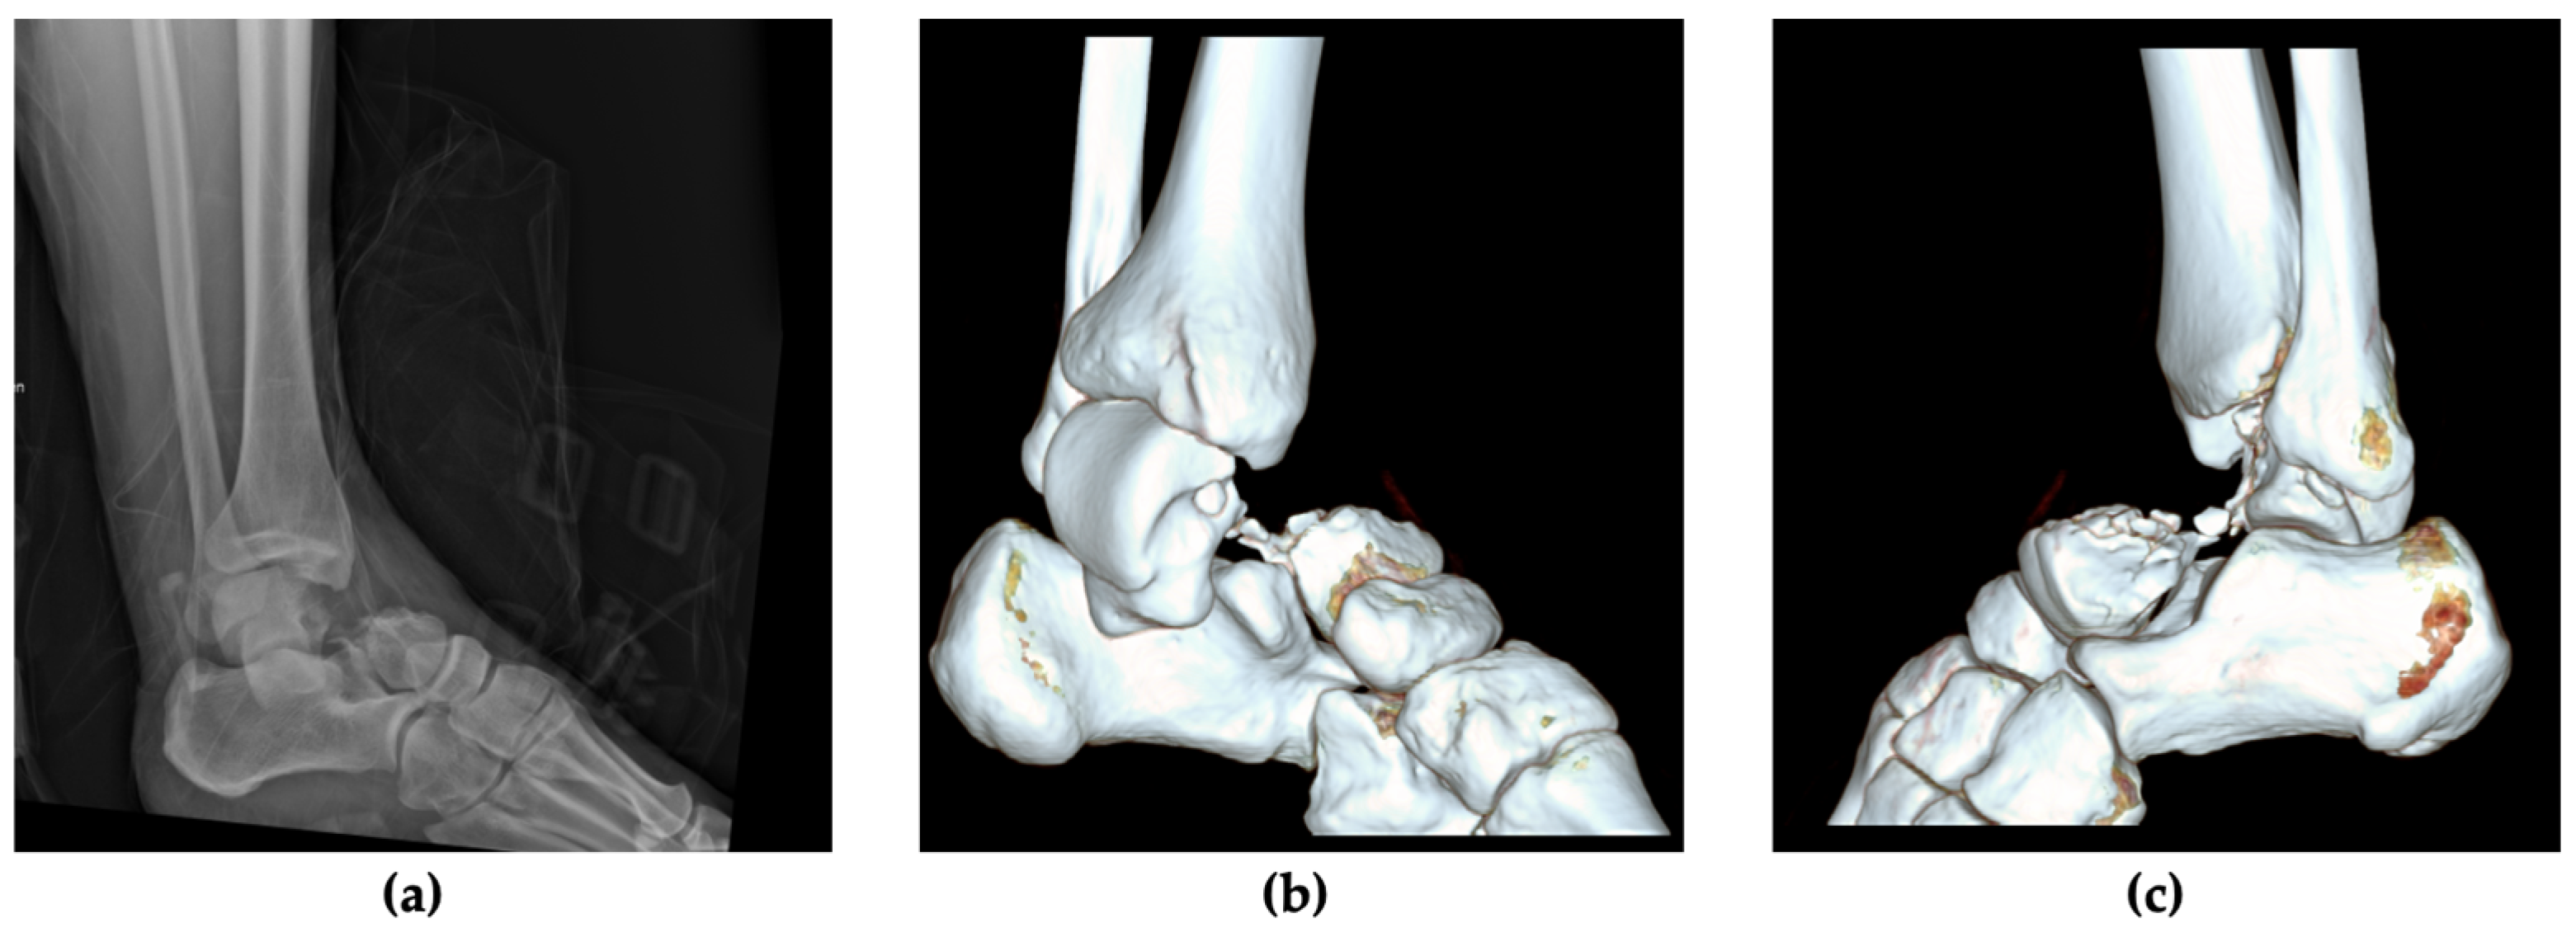

2.1. Patient Information, Clinical Findings and Diagnostic Assessment